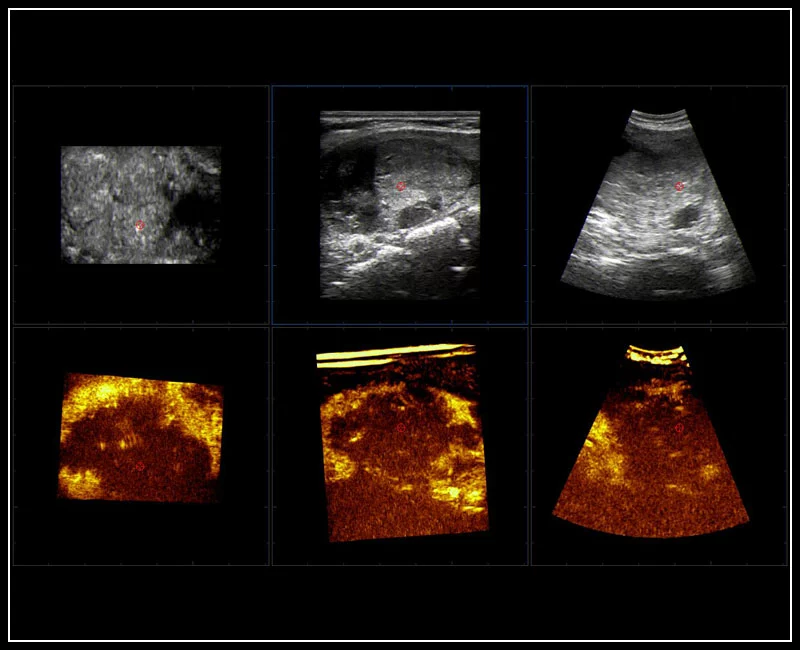

MyLab™9 Platform - QPack CnTI™ perfusion analysis post RF ablation

MyLab™9 Platform - QPack CnTI™ perfusion analysis post RF ablation